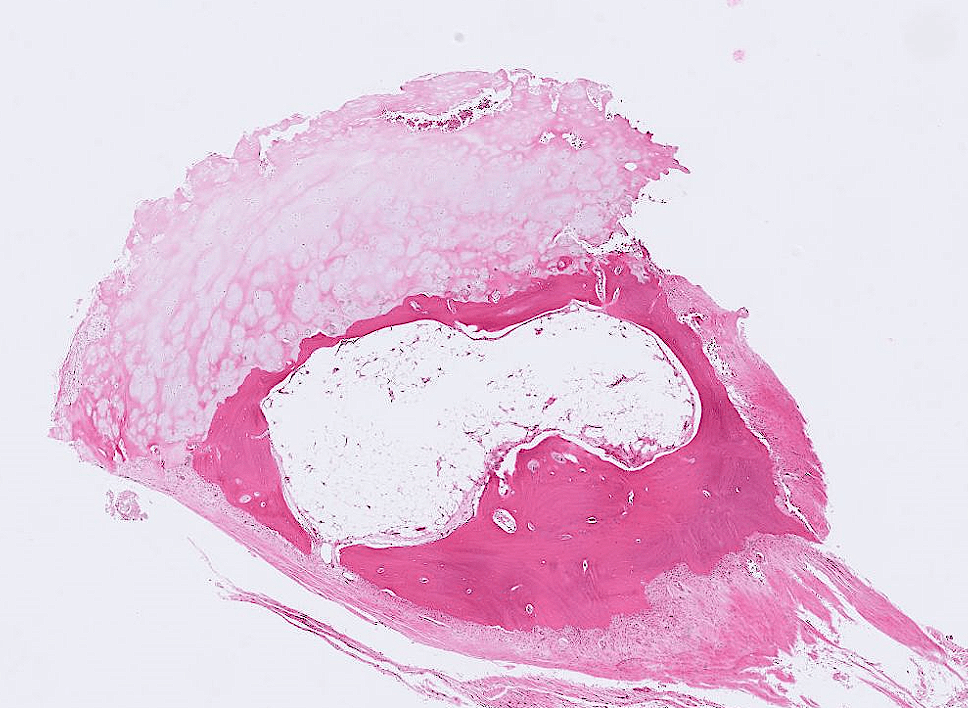

lung adenocarcinoma